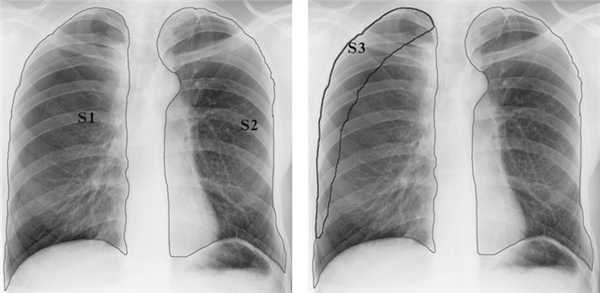

Всем больным выполняли контрольную обзорную рентгенограмму органов грудной клетки в течение 2 ч после экстубации трахеи, непосредственно перед и после удаления плевральных дренажей, а при сохранении недостаточности аэростаза - каждые 2-3 сут в зависимости от клинической ситуации. МСКТ органов грудной клетки в раннем послеоперационном периоде выполнена 3 больным с длительной недостаточностью аэростаза, поэтому интерпретация результатов этого метода в настоящем исследовании не представлена. При формировании остаточной плевральной полости индекс остаточной плевральной полости (ИОПП) рассчитывали по формуле: ,

где S 1 - площадь правой плевральной полости, S 2 - площадь левой плевральной полости, S 3 - площадь остаточной плевральной полости. Перечисленные показатели измеряли по прямой рентгенограмме (рис. 1), используя программу MultiVox 2.0.3701 («Альда Универсал», 2009-2009), так как именно это исследование выполняли всем больным в динамике после операции. Рисунок 1. Расчет индекса остаточной плевральной полости у больного после операции на правом легком.